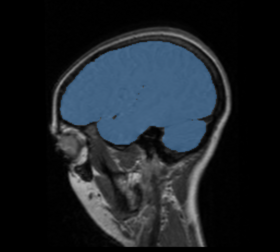

BRAINSMush uses the Maximize Uniformity Summation Heuristic(MUSH) optimizer, as developed at the University of Iowa, to extract the brain and surface CSF from a multi-modal imaging study. It forms a linear combination of multi-modal MR imaging data to make the signal intensity within the brain as uniform as possible. This resulting image is then thresholded to obtain the brain and surface CSF region.

The image is thresholded by the mean signal intensity plus-or-minus five standard deviations.

This method was applied to a sample of 20 MR brain scans and its results were compared to those obtained by 3dSkullStrip, 3dIntracranial, BET and BET2. The average Jaccard metrics for the twenty subjects was 0.66(BET), 0.61(BET2), 0.88(3dIntracranial), 0.91(3dSkullStrip) and 0.94(MUSH).